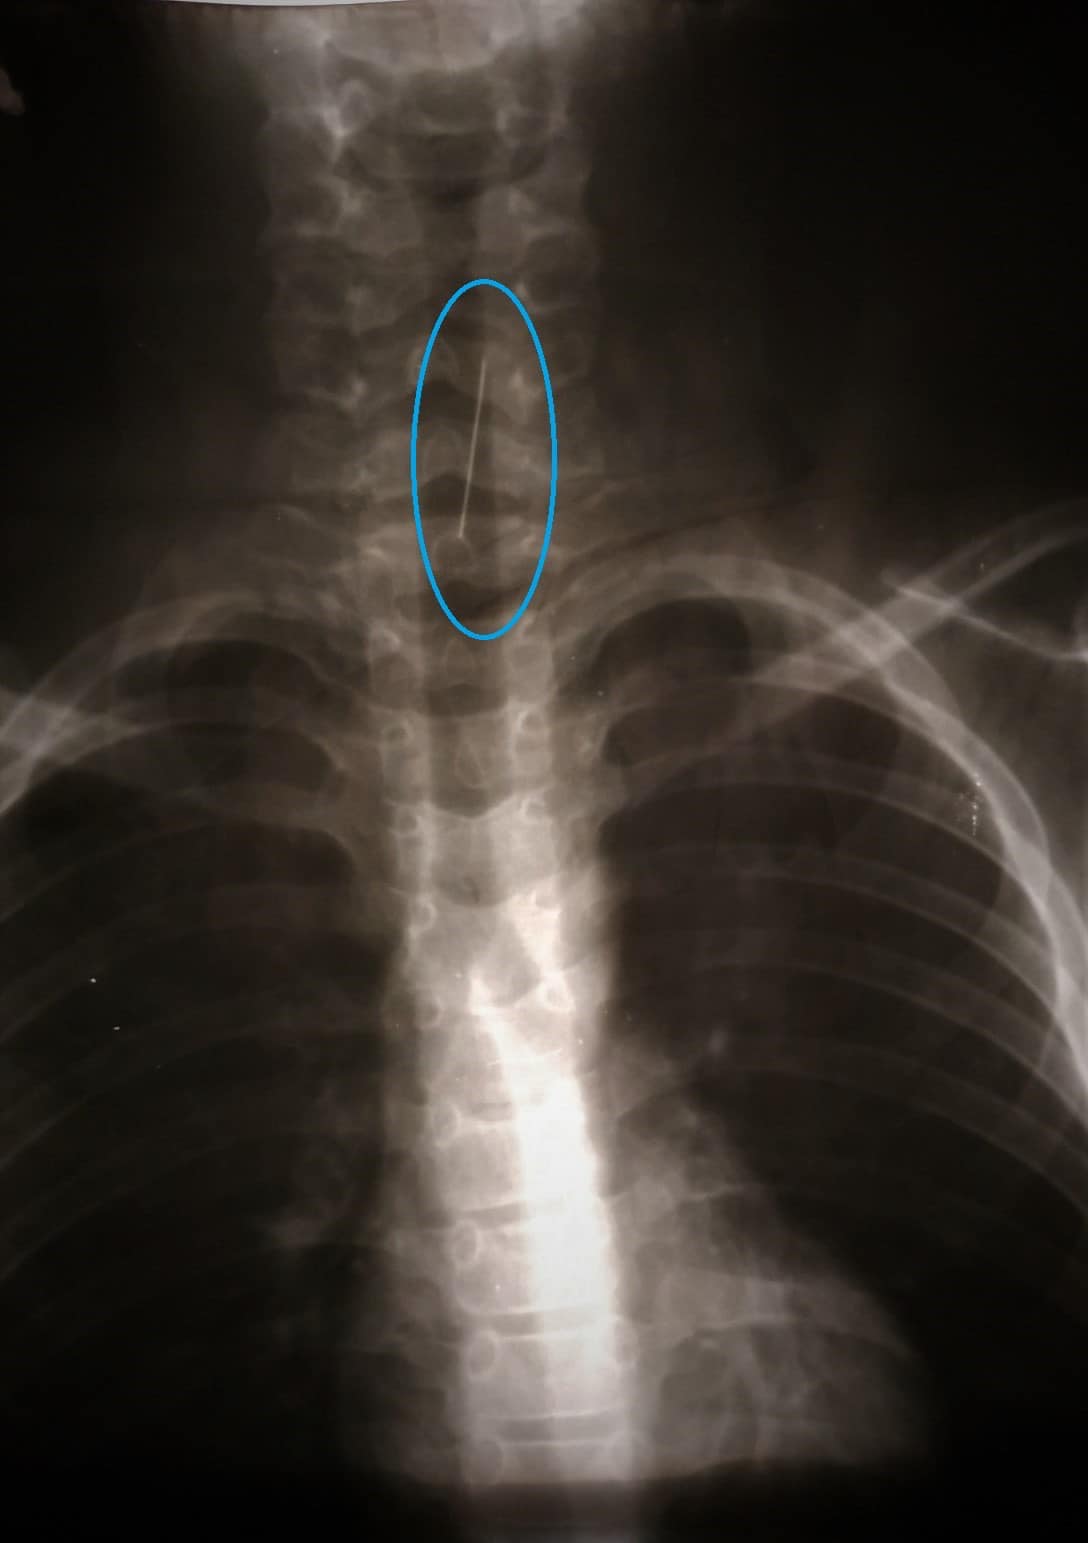

Как сообщают сотрудники Днепропетровской областной детской больницы, вечером 28 октября к ним привезли ребенка, который по неосторожности проглотил булавку. Чтобы выяснить, где именно находится инородный предмет, врачи провели при помощи эндоскопа (осветительно-оптического прибора) исследование горла ребенка. В итоге они обнаружили, что швейная шпилька прикололась к трахее. Выглядело это так:

В Днепре спасали ребенка, который проглотил булавку/ фото: facebook.com/Дніпропетровська обласна дитяча лікарня В Днепре спасали ребенка, который проглотил булавку/ фото: facebook.com/Дніпропетровська обласна дитяча лікарня